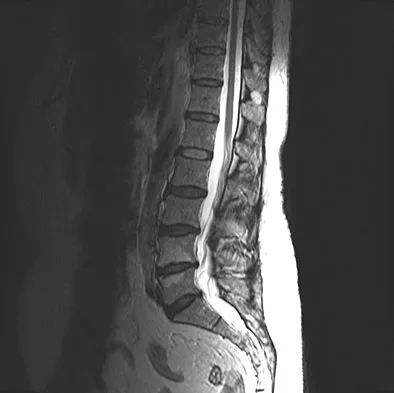

Question 90

Figures 1a through 1c show the radiograph and MRI scans of a 16-year-old patient who has a painful hip. Examination reveals a significant limp, limited abduction and internal rotation, and severe pain with internal rotation and adduction. A biopsy specimen is shown in Figure 1d. What is the deposited pigment observed in this condition?

Explanation